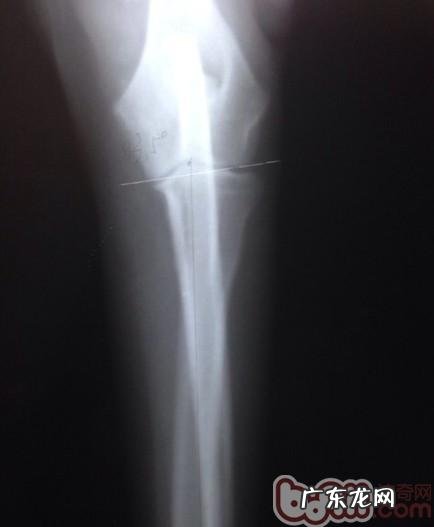

医治层面 , 宠物医生临床医学上也历经长期的科学研究 , 许多 脑外科宠物医生师在这儿推本溯源 。有的宠物医生师为了更好地使骨节承受力匀称在一个平行线上 , 甘愿把肱骨断开再再次接好 , 也得到 过一定的实际效果 。

文章插图

犬腕关节发育不全